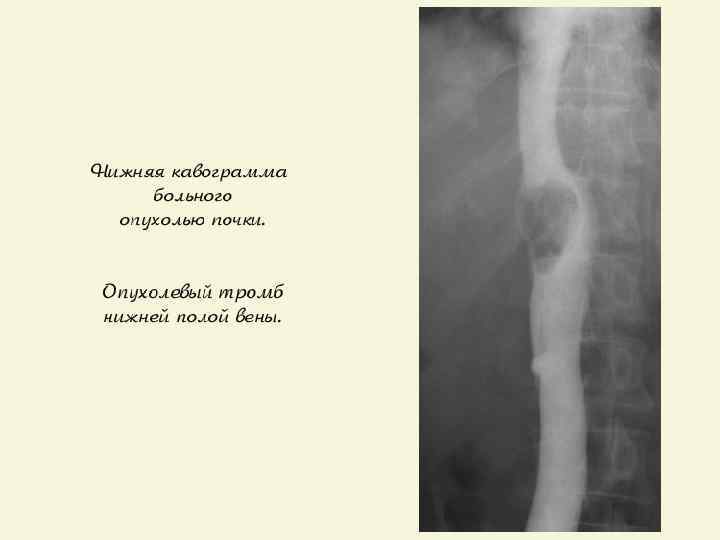

КЛИНИЧЕСКИЕ ПРИЗНАКИ И СИМПТОМЫ q Ранние стадии протекают бессимптомно, не пальпируются и обнаруживаютcя случайно при УЗИ почек; q Симптомы: - «триада симптомов» : гематурия, боль, пальпируемая опухоль; - синдром сдавления НПВ (при опухолевом тромбозе или компрессии опухолью/ увеличенными ЛУ): отёки ног, варикоцеле, расширение подкожных вен живота, тромбоз глубоких вен нижних конечностей, протеинурия; - нефрогенная артериальная гипертензия.

КТ – опухолевый тромбоз нижней полой вены.

ДИАГНОСТИКА § Дополнительные методы диагностики используются по показаниям (наличие клинической симптоматики или лабораторные признаки): - остеосцинтиграфия, МРТ или КТ головного мозга, почечная ангиография, кавография - тонкоигольная биопсия опухоли.

ЛЕЧЕНИЕ ПОЧЕЧНО – КЛЕТОЧНОГО РАКА q Радикальная нефрэктомия (РН) – «золотой» стандарт лечения локализованного ПКР; q В настоящее время нет преимуществ трансабдоминального перед трансперитонеальным доступом; q Адреналэктомия рекомендуется, если есть опухоль в/полюса почки или КТ-признаки распространения ПКР на надпочечник; q Лимфаденэктомия (ЛАЭ) используется только для определения стадии заболевания (N), т. к. расширенная ЛАЭ не улучшает выживаемость; q ПКР с опухолевым тромбом без MTS имеет лучший прогноз после РН и полной тромбэктомии из НПВ, чем при прорастании стенки НПВ.

ТРОМБЭКТОМИЯ ИЗ НПВ